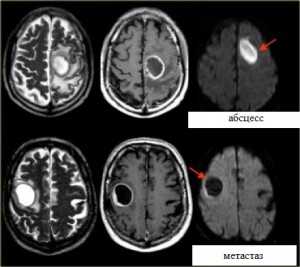

Диффузия:

Яркие очаги на диффузионное-взвешенных МРТ изображениях характерны для абсцессов, эпидермоидных кист, и острого инсульта. Опухоли имеют низкий сигнал на ДВИ МРТ головного мозга.![Диффузия-обр]()

МРТ головного мозга. Аксиальные Т2-взвешенные МРТ, Т1-взвешенные МРТ с контрастировавшем и ДВИ МРТ.